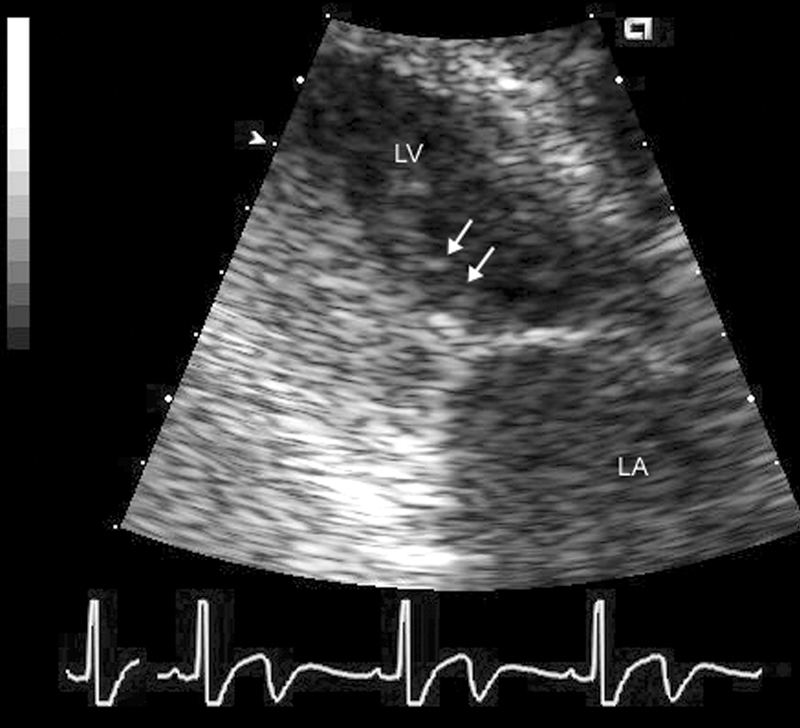

فحوصات تشخيصية لبعض امراض القلب والشرايين التاجية